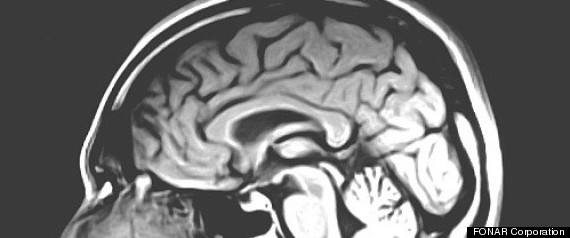

The brain may not seem like an obvious place to look for possible treatments for obesity, but researchers say implanting a device that stimulates a specific region of the brain may help curb the compulsion to overeat.

The new study on obese mice found that deep brain stimulation (DBS), which involves implanting a device that sends electrical impulses to precise targets in the brain, may reduce binge eating and other obesity-related behaviors.